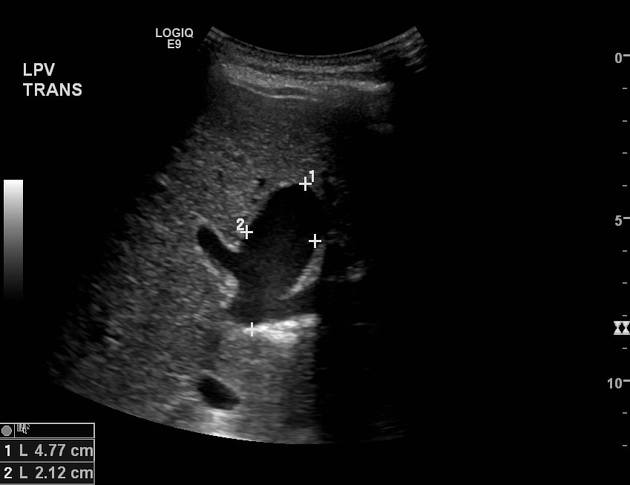

Phình TM cửa

» Thông tin: Nam giới – 90 tuổi.

» Lâm sàng: Kiểm tra sức khỏe.